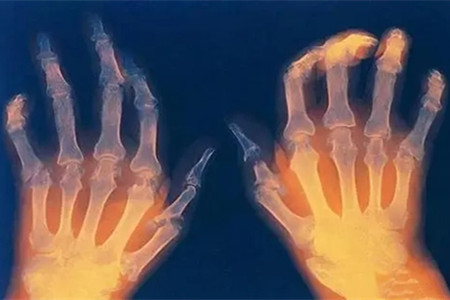

类风湿是一种以慢性、全身炎症性、侵蚀性关节炎为特征的自身免疫性疾病,属于弥漫性结缔组织病的一种。类风湿的临床特征是关节变形和肿痛,对患者的生活和工作造成了严重影响。

本病好发年龄段为50岁以上,主要累及膝、脊柱等负重关节,活动时关节疼痛加重,可引发关节肿胀和积液。手指骨关节炎常被误诊为类风湿,尤其是在远端指间关节和近端指关节出现结节时易被视为滑膜炎。该病通常无游走性疼痛,大多数患者血沉正常,X线显示关节间隙狭窄、关节边缘呈唇样增生。